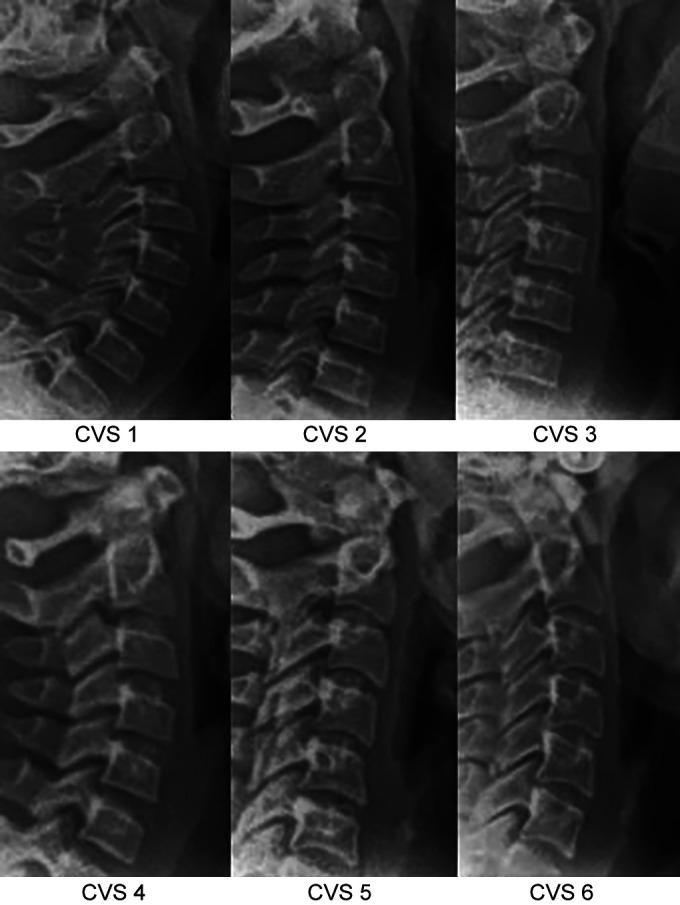

The aim of the present study was to investigate the relationships between the skeletal age (SA), dental age (DA), and CA along with the stages of calcification of teeth and the cervical vertebral maturity (CVM) stages in Indian subjects.

A sample of 100 pairs preexisting radiographs, both orthopantomogram and lateral cephalogram, of the individuals in the age-group of 8-15 years were procured and were analyzed for the level of dental and skeletal maturity using Demirjian scale and cervical vertebral maturity index, respectively.

本研究的目的是调查印度受试者的骨骼年龄(SA)、牙齿年龄(DA)和实足年龄之间的关系,以及牙齿钙化阶段和颈椎成熟度(CVM)阶段之间的关系。

收集了100对8至15岁个体的现有口腔全景片和头颅侧位片,分别使用德米尔坚量表和颈椎成熟度指数分析牙齿和骨骼的成熟水平。